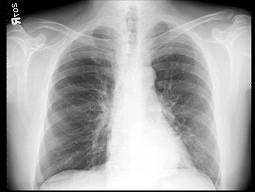

60岁,男,体检胸片发现异常,CT检查如图,请选出最可能的诊断 ( )A、韦格肉芽肿B、支气管腺瘤C、错构瘤D、肺结核E、肺癌

问题 60岁,男,体检胸片发现异常,CT检查如图,请选出最可能的诊断 ( )

选项 A、韦格肉芽肿 B、支气管腺瘤 C、错构瘤 D、肺结核 E、肺癌

答案 E